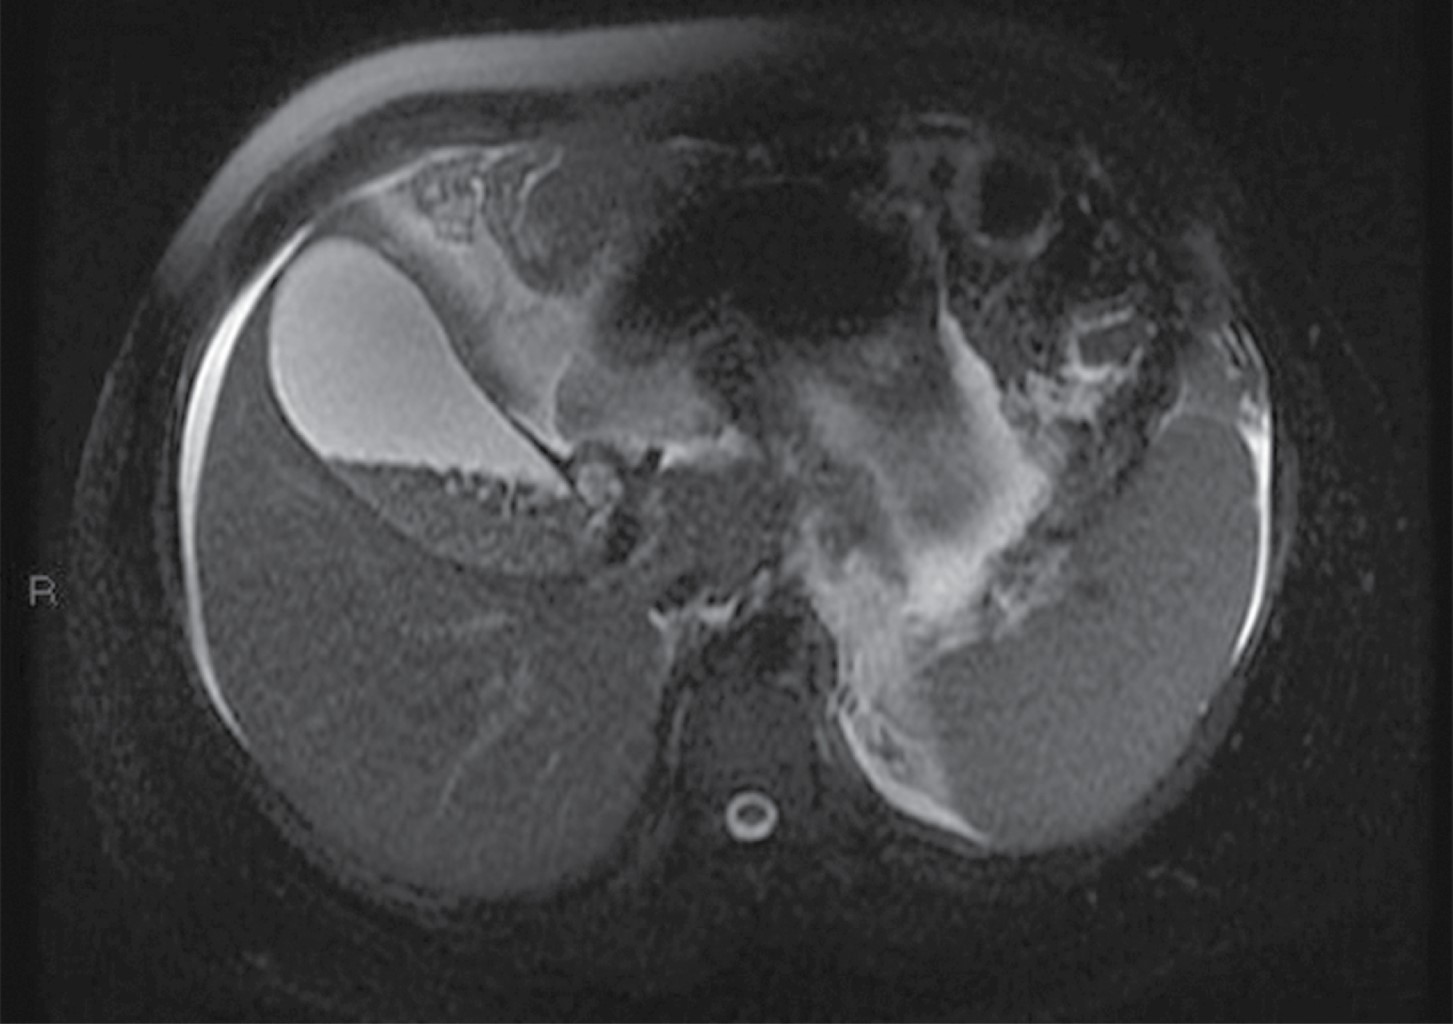

Masculino de 32 años de edad, sin antecedentes personales patológicos de importancia, acude al servicio de urgencias por presentar dolor abdominal transfictivo a nivel de epigastrio, acompañado de vómito de contenido alimenticio en dos ocasiones. Se solicitó estudio de tomografía abdominal por médico tratante, la cual se realizó con modalidad de energía dual, y definió múltiples imágenes redondeadas en vesícula biliar en relación a litiasis (Figura 1) así como aumento del volumen pancreático y estriación de la grasa adyacente compatible con pancreatitis Balthazar D (Figura 2).

El estudio imagenológico de la litiasis vesicular tiene vital importancia en el manejo de los pacientes con abdomen agudo de los servicios de urgencias.3 La tomografía computarizada de abdomen ha sido establecida como una herramienta primordial de imagenología en el proceso diagnóstico en diversas patologías abdominales y como una herramienta con gran sensibilidad y especificidad en la valoración del abdomen agudo,5 aunque de forma inicial el ultrasonido continúa siendo el estudio de primera elección en pacientes con historia reciente de dolor de tipo biliar, con una especificidad superior a 95% para litos mayores de 2 mm.1,2 En la resonancia magnética la litiasis vesicular se observa mejor en imágenes contrastadas en T2 (Figura 3), e incluso puede ayudar a distinguir entre diferentes tipos de cálculos biliares, los de colesterol tienden a tener mayor intensidad en T1, mientras que los cálculos pigmentados al igual que los de colesterol tienden a ser hipointensos en secuencias en T2, lo cual tiene implicaciones terapéuticas.2,6